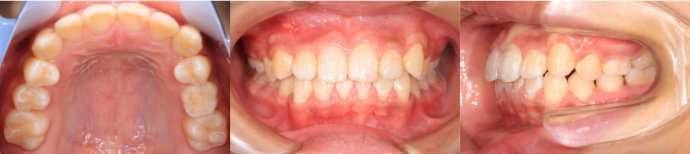

| Case5 |

| 前歯のガタガタ |

| <治療前> |

| <治療後> |

| 主訴 |

上下の前歯の乱れが気になる |

| 診断名 |

叢生 |

| 年齢 |

10歳 |

| 使用装置 |

マルチブラケット装置 |

| 抜歯部位 |

永久歯の抜歯は無し |

| 治療期間 |

2年6か月 |

| 治療費概算 |

検査・診断料:5万円+税 装置・技術料:25万円+税 おおよそ1か月ごとの処置・管理料:5,000円+税 保定装置料:5万円+税 |

| リスク・副作用 |

特になし |